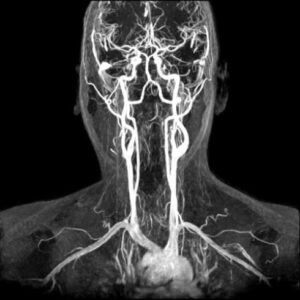

La sua elevata definizione consente inoltre un appropriato studio delle sezioni destre del cuore spesso di difficile valutazione con altre metodiche, ecocardiografia compresa. Qualora la tecnica venga applicata al distretto vascolare, generalmente per la definizione di anomalie di decorso o diametro di arterie, si parla di ANGIORM specificandone il distretto (ad es cerebrale, toracico, addominale…).